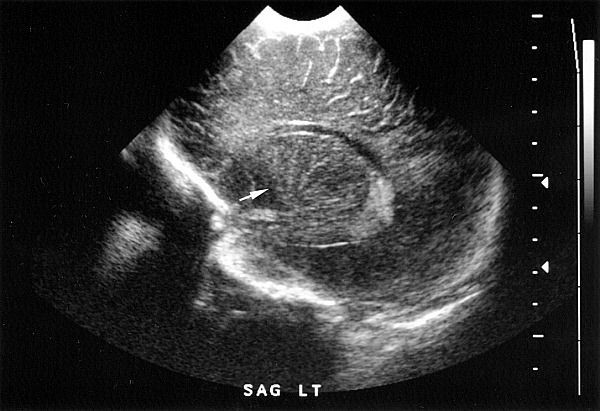

Neonatology Lenticulostriate Vasculopathy 2 Image